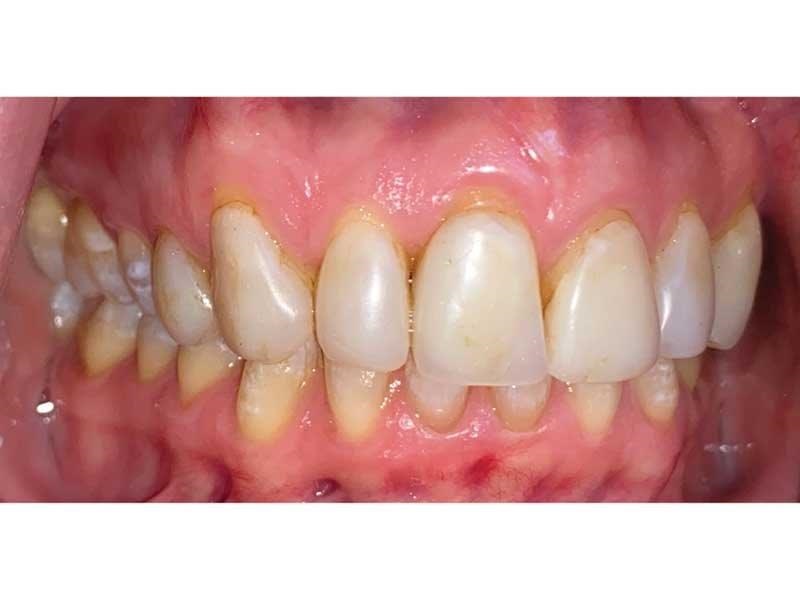

Meet Lorraine, who came into my office to “redo her bonding.” Lorraine had some upper anterior teeth done years ago with resin, which now was dull, stained and breaking down (Figs. 1–3). She had an amount of money in mind that she thought it would cost. She was very wrong.

The big challenge: Retruded and overclosed. Lorraine looked retruded and overclosed, so I started to ask her about headaches, jaw issues and chronic pain. As we talked, she revealed that she had been in severe pain her whole life. She had all the signs and symptoms of TMD and had been to multiple doctors, pain clinics, alternative medicine practitioners, massage therapists, chiropractors, osteopaths … you name it.

Fig. 1

Fig. 2

Fig. 3